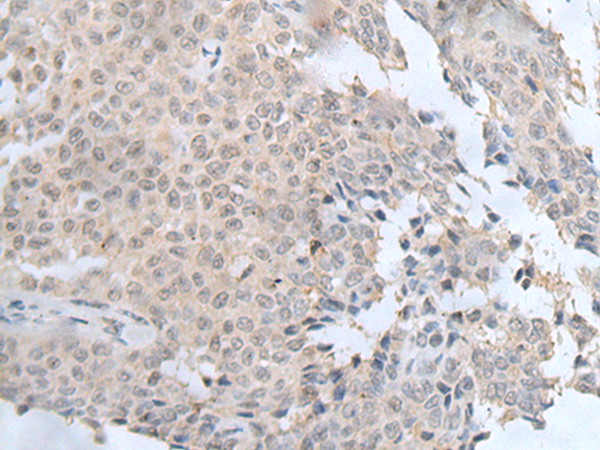

IHC positive control:

Human colorectal cancer and human ovarian cancer